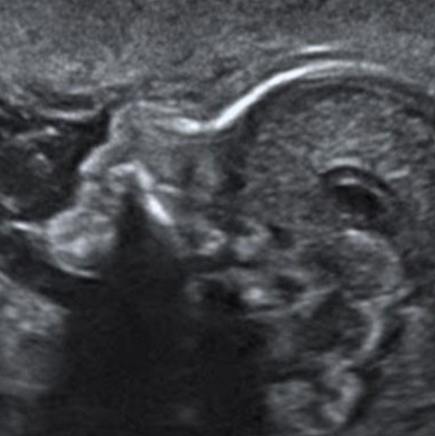

סקירה מערכות מאוחרת

יש לעשות בין השבוע ה־20 לשבוע ה־23 להיריון

סקירת מערכות מאוחרת (שנקראת גם “סקירה שנייה”) היא בדיקת אולטרסאונד הסוקרת את האיברים של העובר במטרה לאתר מומים וממצאים לא תקינים